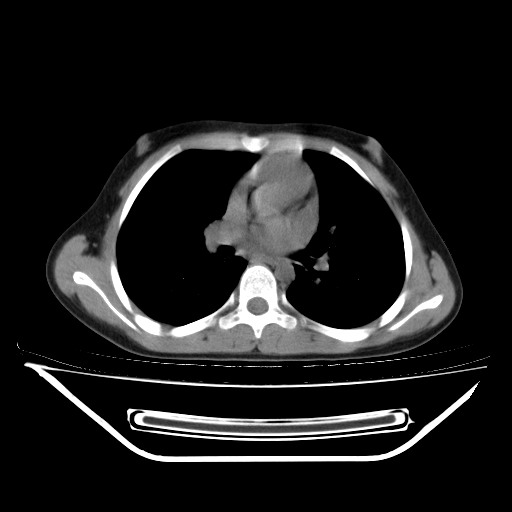

经过胸部穿刺活检为支原体感染。以下示抗支原体感染30天后所见,病灶明显缩小,临床症状消失: